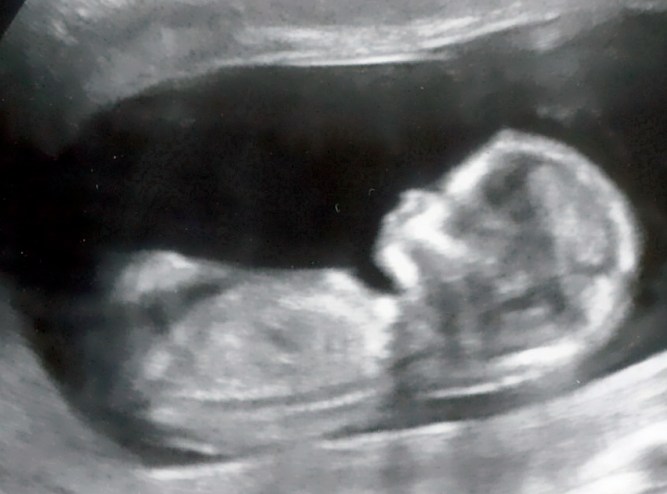

At first, it didn’t really seem all that real to me. First trimester was not at all enjoyable. It seemed like it was all symptoms and no point to them whatsoever. For all I knew, I was simply suffering from multiple chronic issues including indigestion, constant nausea (wouldn’t it be nice if it were ACTUALLY confined to only mornings?), loss of fitness, general fatigue, and unexplainable weight gain. The excitement was virtually non-existent… except for when I was talking to Kerry, James’ mother and Baby Snare’s grandma-to-be! I did have the 12 week ultrasound (I told my husband that my only goal for that ultrasound was simply to get proof that there actually was a baby inside me!) but whilst it had its magical moments, after it was over it still felt like I was simply watching someone else’s baby video.

(16 weeks)